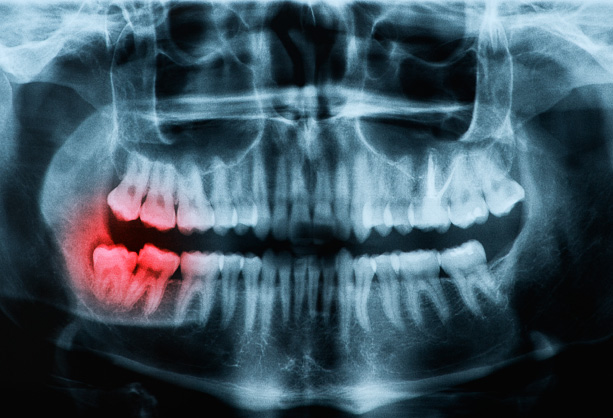

Wisdom teeth extraction at Nebras Medical Center in Ras Al

Khaimah removes impacted third molars that cause pain or

infection.

Performed under local or general anesthesia, the procedure alleviates symptoms and prevents complications. Post-surgery care involves managing pain, following a soft-food diet, and maintaining oral hygiene for proper healing.